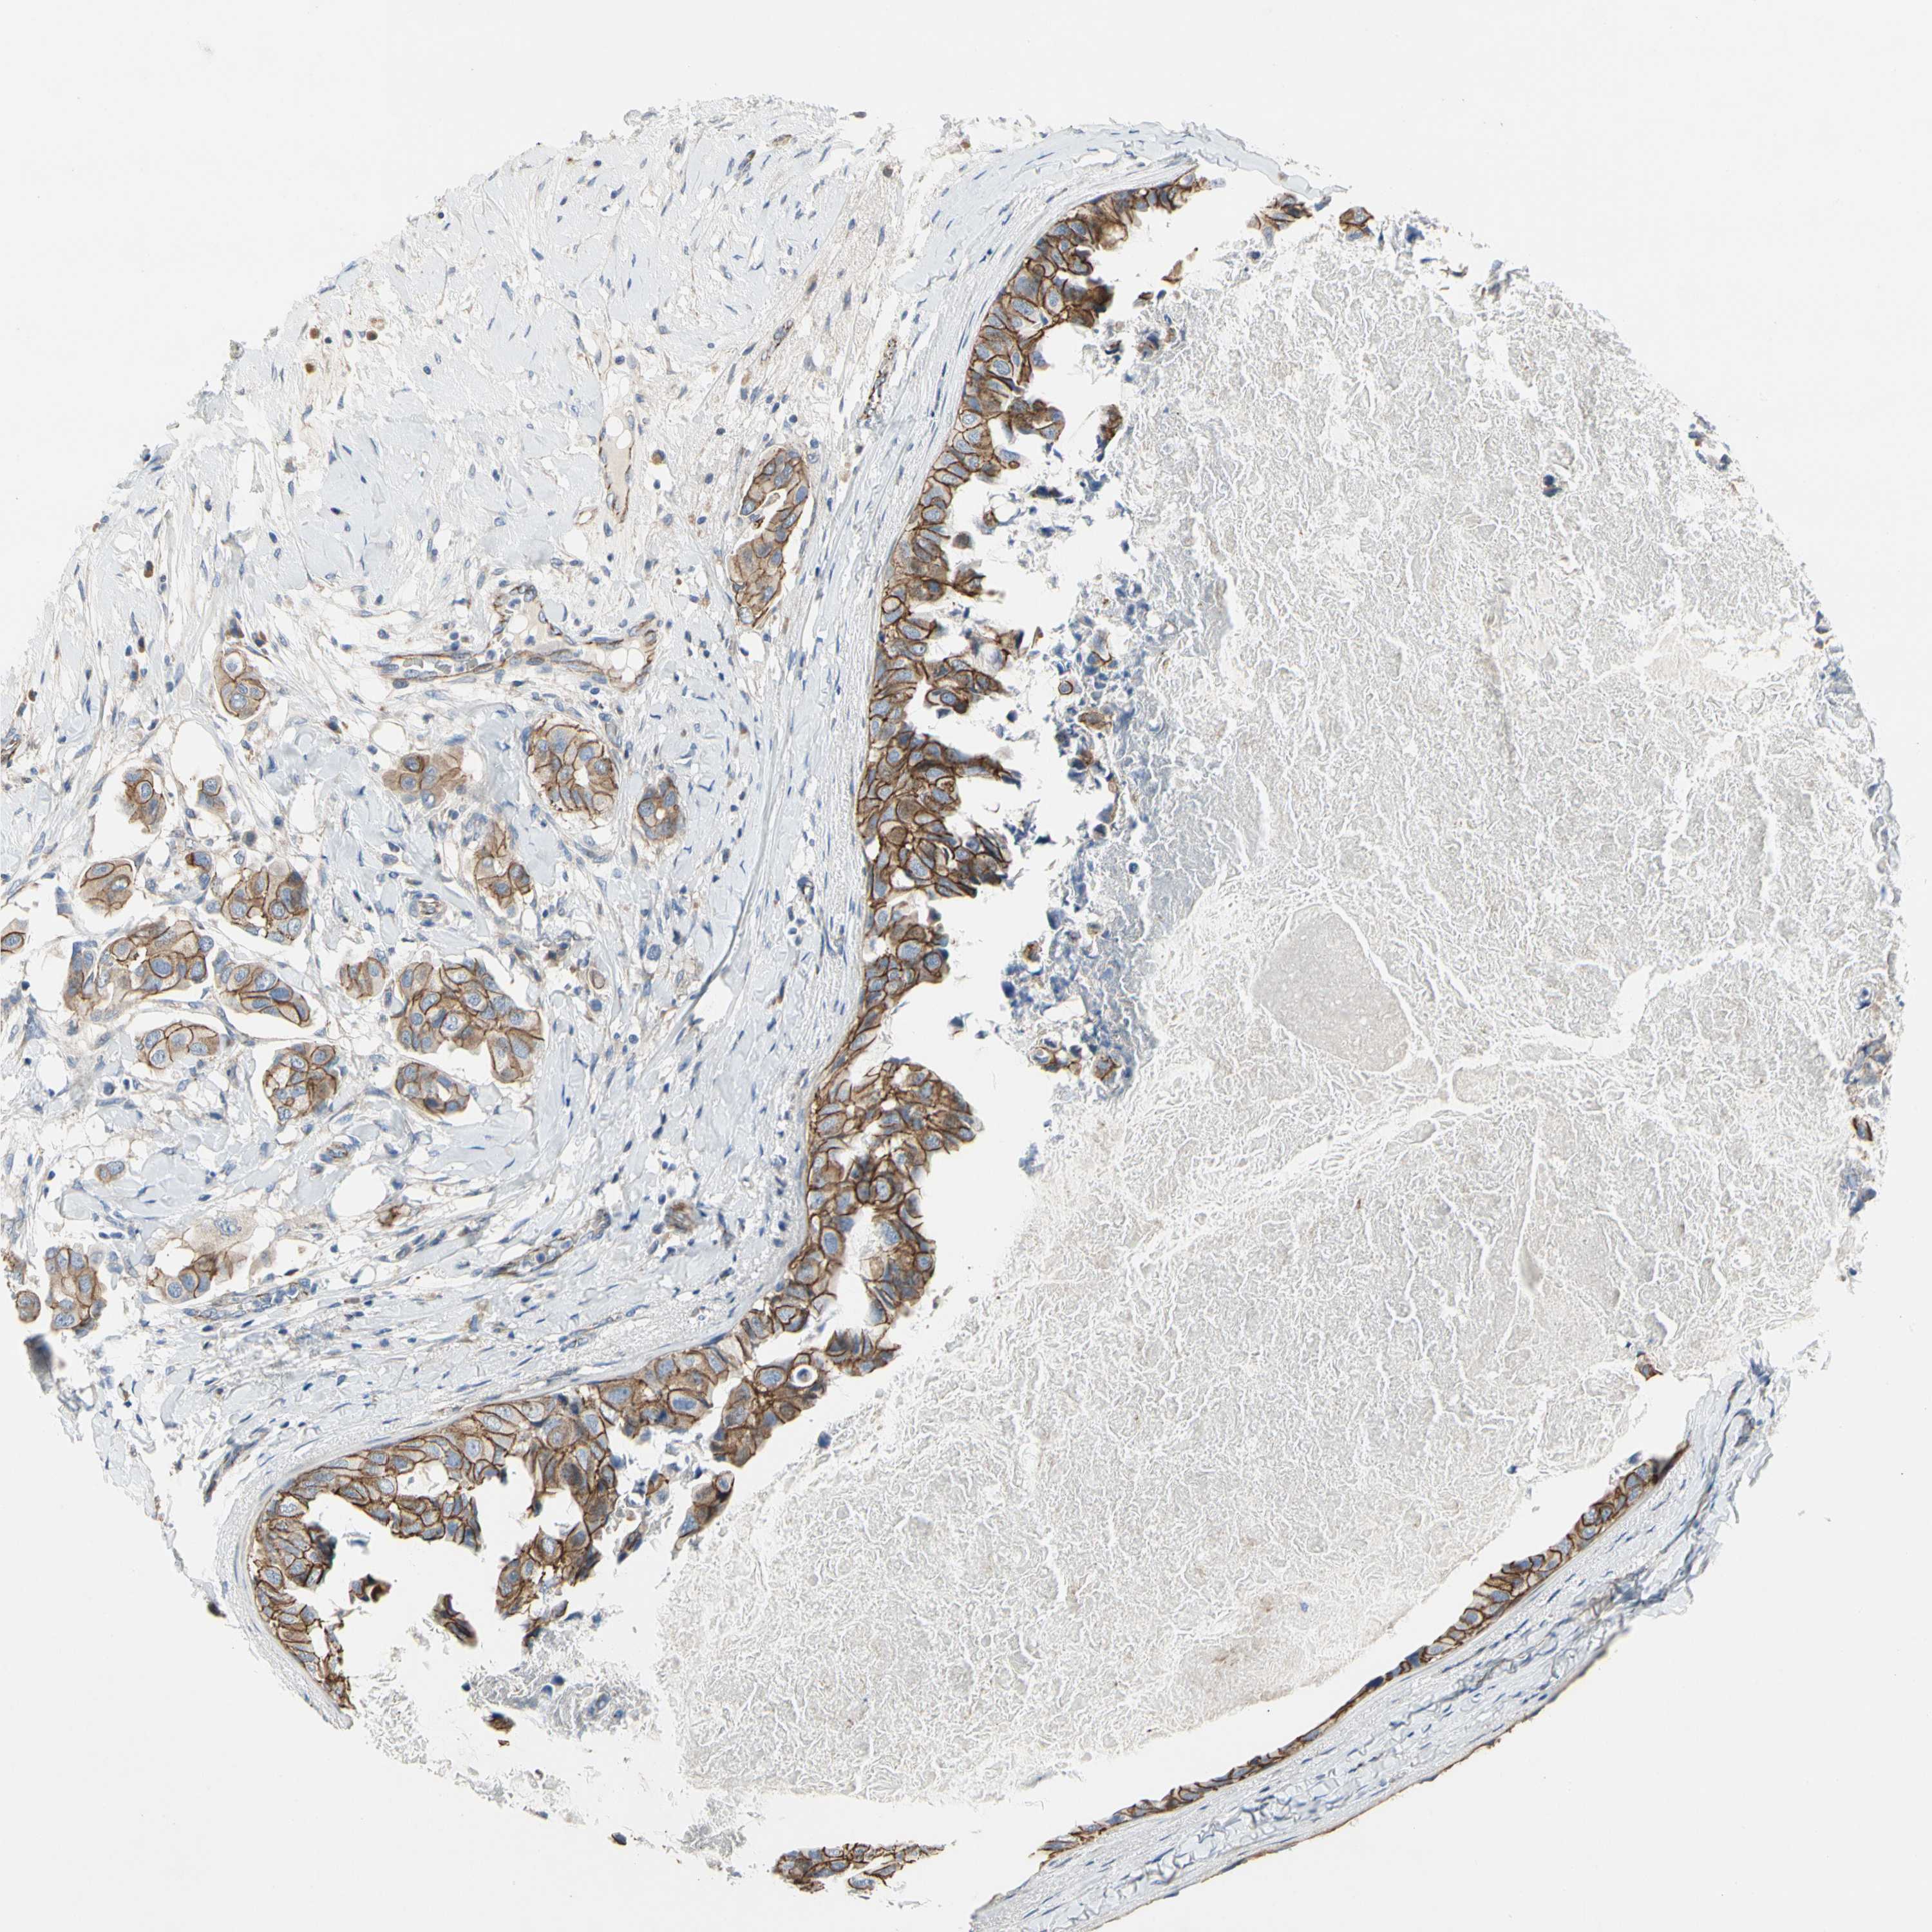

CANCER BREAST CANCER Show tissue menu

BRCA TCGA BRCA VALIDATION PROTEIN EXPRESSION

ANTIBODIES

AND

VALIDATION

LGR6 is potential prognostic, high expression is favorable in Breast Invasive Carcinoma (TCGA)